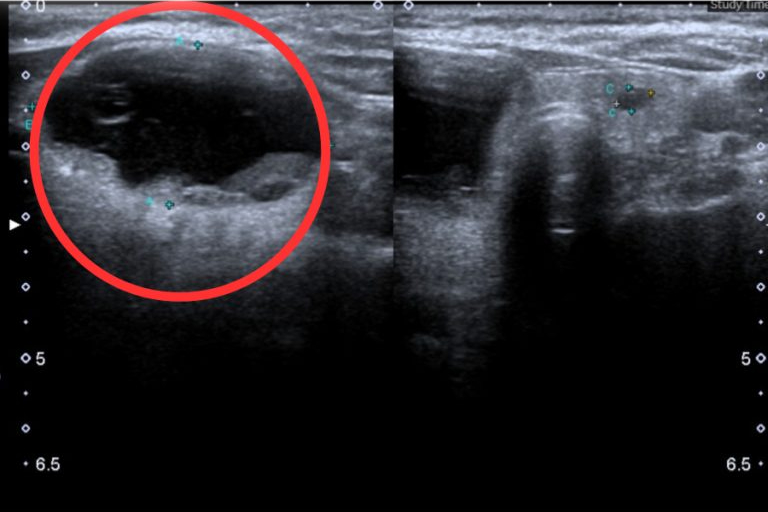

צילום אולטרסאונד של בלוטת התריס. צילום: BVCC

תוצאות אולטרסאונד של בלוטת התריס הראו כי באונה הימנית-מצר הישנה ובאונה השמאלית של המטופל היו מבנים מוצקים וציסטיים במידות של 42 מ"מ על 23 מ"מ ו-3.4 מ"מ על 5.1 מ"מ. המטופל אובחן עם ציסטה דו-אונתית בבלוטת התריס ומצר תריס טיראדס 1 (רקמת בלוטת תריס בריאה). לאחר התייעצות, הרופאים החליטו לבחור באפשרות של ניתוח אנדוסקופי להסרה חלקית של האונה הימנית והמצר הישנה דרך בית השחי-חזה באמצעות חותך אולטרסאונד.